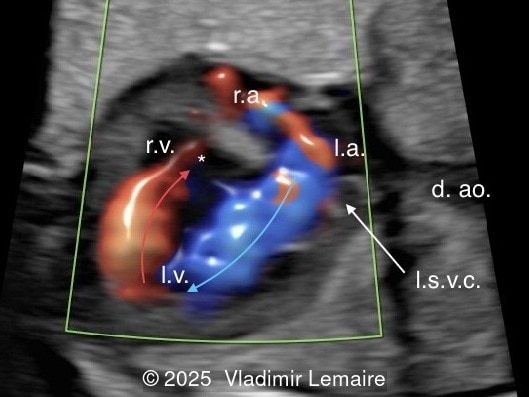

We present a case of isolated tricuspid atresia type 1 with persistent left superior vena cava. No other extracardiac anomalies were found. Our diagnosis was confirmed after birth.

In the images below, the abbreviations are as follows: RA: right atrium; RV: right ventricle; LV: left ventricle; MV: mitral valve; LA: left atrium; FO: foramen ovale; SVC: superior vena cava; LSVC: left superior vena cava; PV: pulmonary veins; PA: pulmonary artery; MPA: main pulmonary artery; RPA: right pulmonary artery; AO: aorta; dAO: descending aorta; aAO: ascending aorta; DA: ductus arteriosus; T: trachea; * marks the ventricular septal defect.

Four-chamber view with color Doppler. Color Doppler confirms the absence of blood flow across the tricuspid valve in diastole.

Image 2 Four-chamber view with color Doppler. Color Doppler confirms the absence of blood flow across the tricuspid valve in diastole.

Four-chamber view with color Doppler. Blood enters the right ventricle across the VSD in late diastole and systole.

Image 3 Four-chamber view with color Doppler. Blood enters the right ventricle across the VSD in late diastole and systole.

Color Doppler confirms the diagnosis on grayscale ultrasound, as it demonstrates the lack of blood flow across the tricuspid valve and a patent mitral valve. Due to increased blood flow across the mitral valve, aliasing is typically noted on color Doppler. Mitral valve regurgitation has been associated with a poor outcome. The right ventricular cavity is filled in late diastole from the left ventricle, through the ventricular septal defect. Left-to-right shunting across the ventricular septal defect can be seen on color Doppler. Color Doppler is helpful in the evaluation of flow across the great arteries. Flow across the pulmonary artery is generally antegrade. Pulmonary stenosis should be suspected when the vessel is diminutive in size rather than the demonstration of turbulent flow on color Doppler, which is typically absent in these cases.